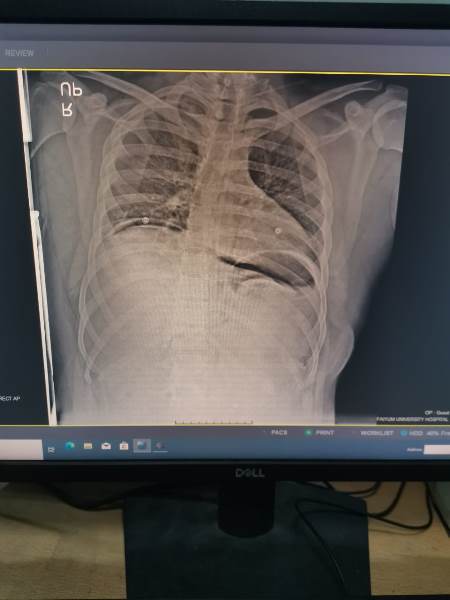

حالة استكشاف بالصدر لمريض تعرض لطعنة نافذة أدي الي تجمع دموي وهوائي بالصدر وهبوط حاد بالدورة الدموية

تبين وجود إصابة للرئة والحجاب الحاجز واحد الشرايين الرئيسية المغذية للصدر.